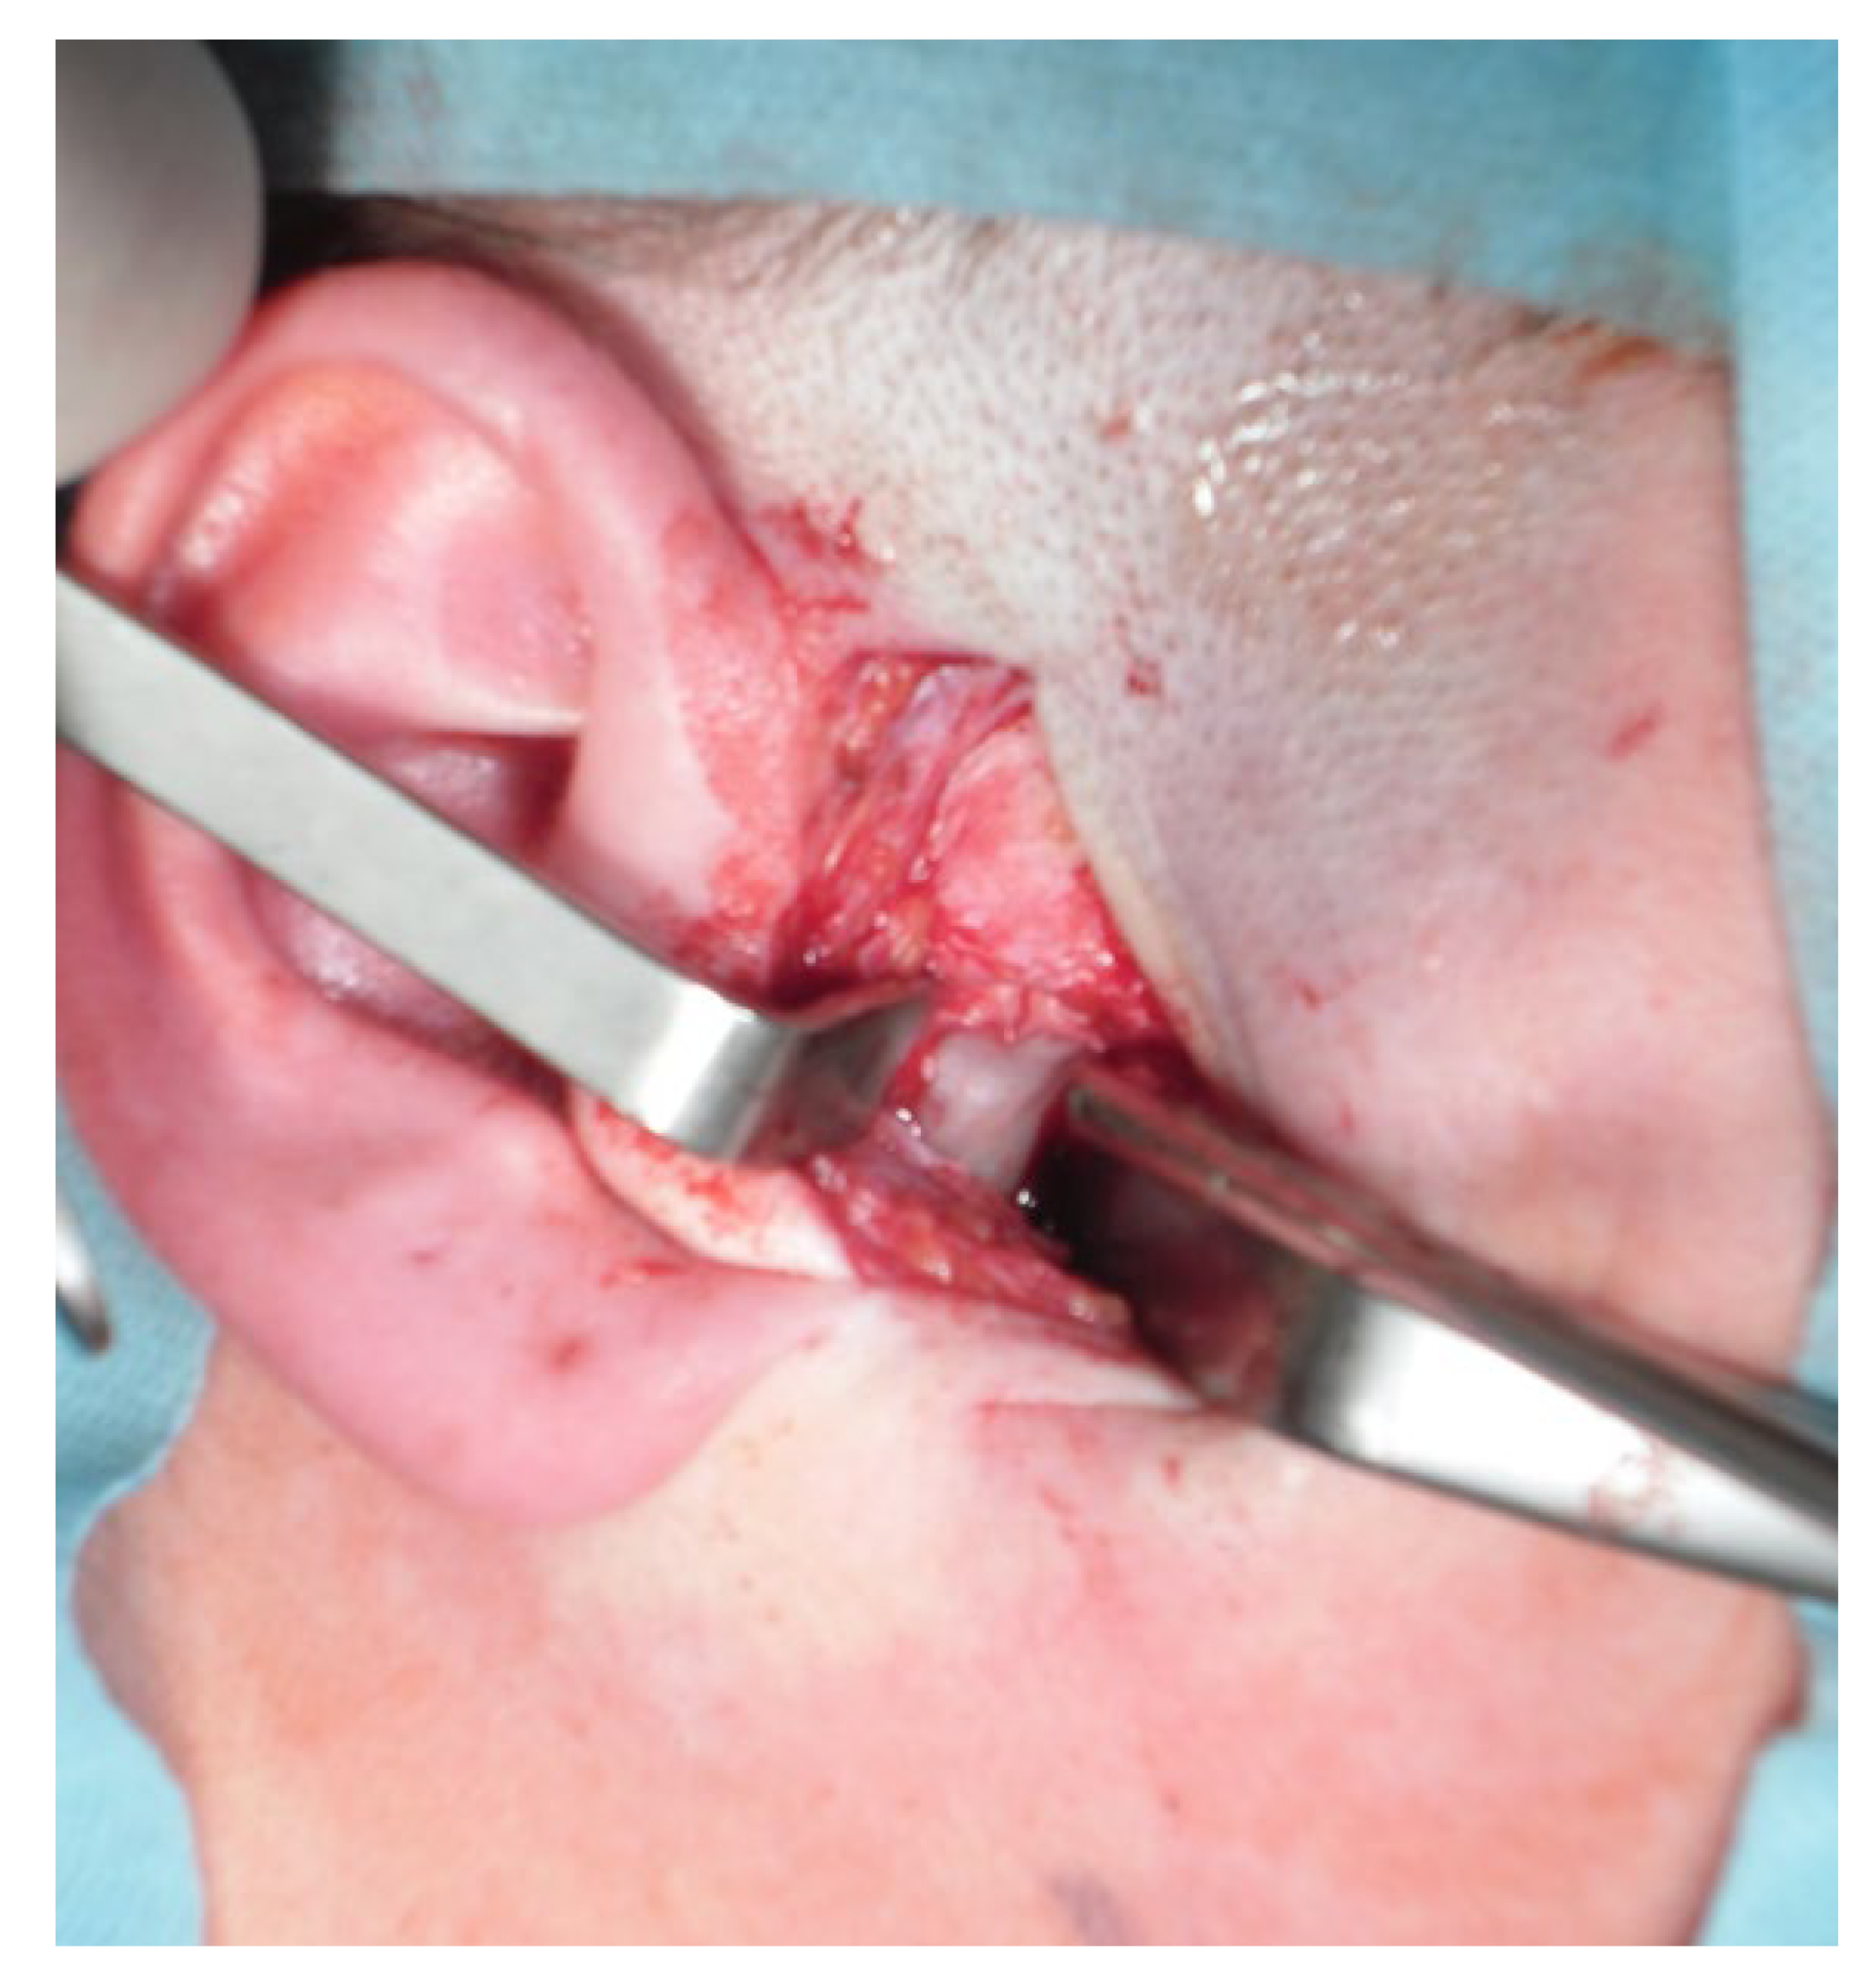

- A condylectomy with BSSO and Lefort I simultaneously was described by Wolford in 2002; however, some authors report operated TMJ joint instability, which might be related to the degree of excised bone and poor condyle stabilization with at least lateral pterygoid muscle reattachment or other, perhaps even related with IMF intramaxillary fixation devices to stabilize the occlusion [75] (Figure 9);